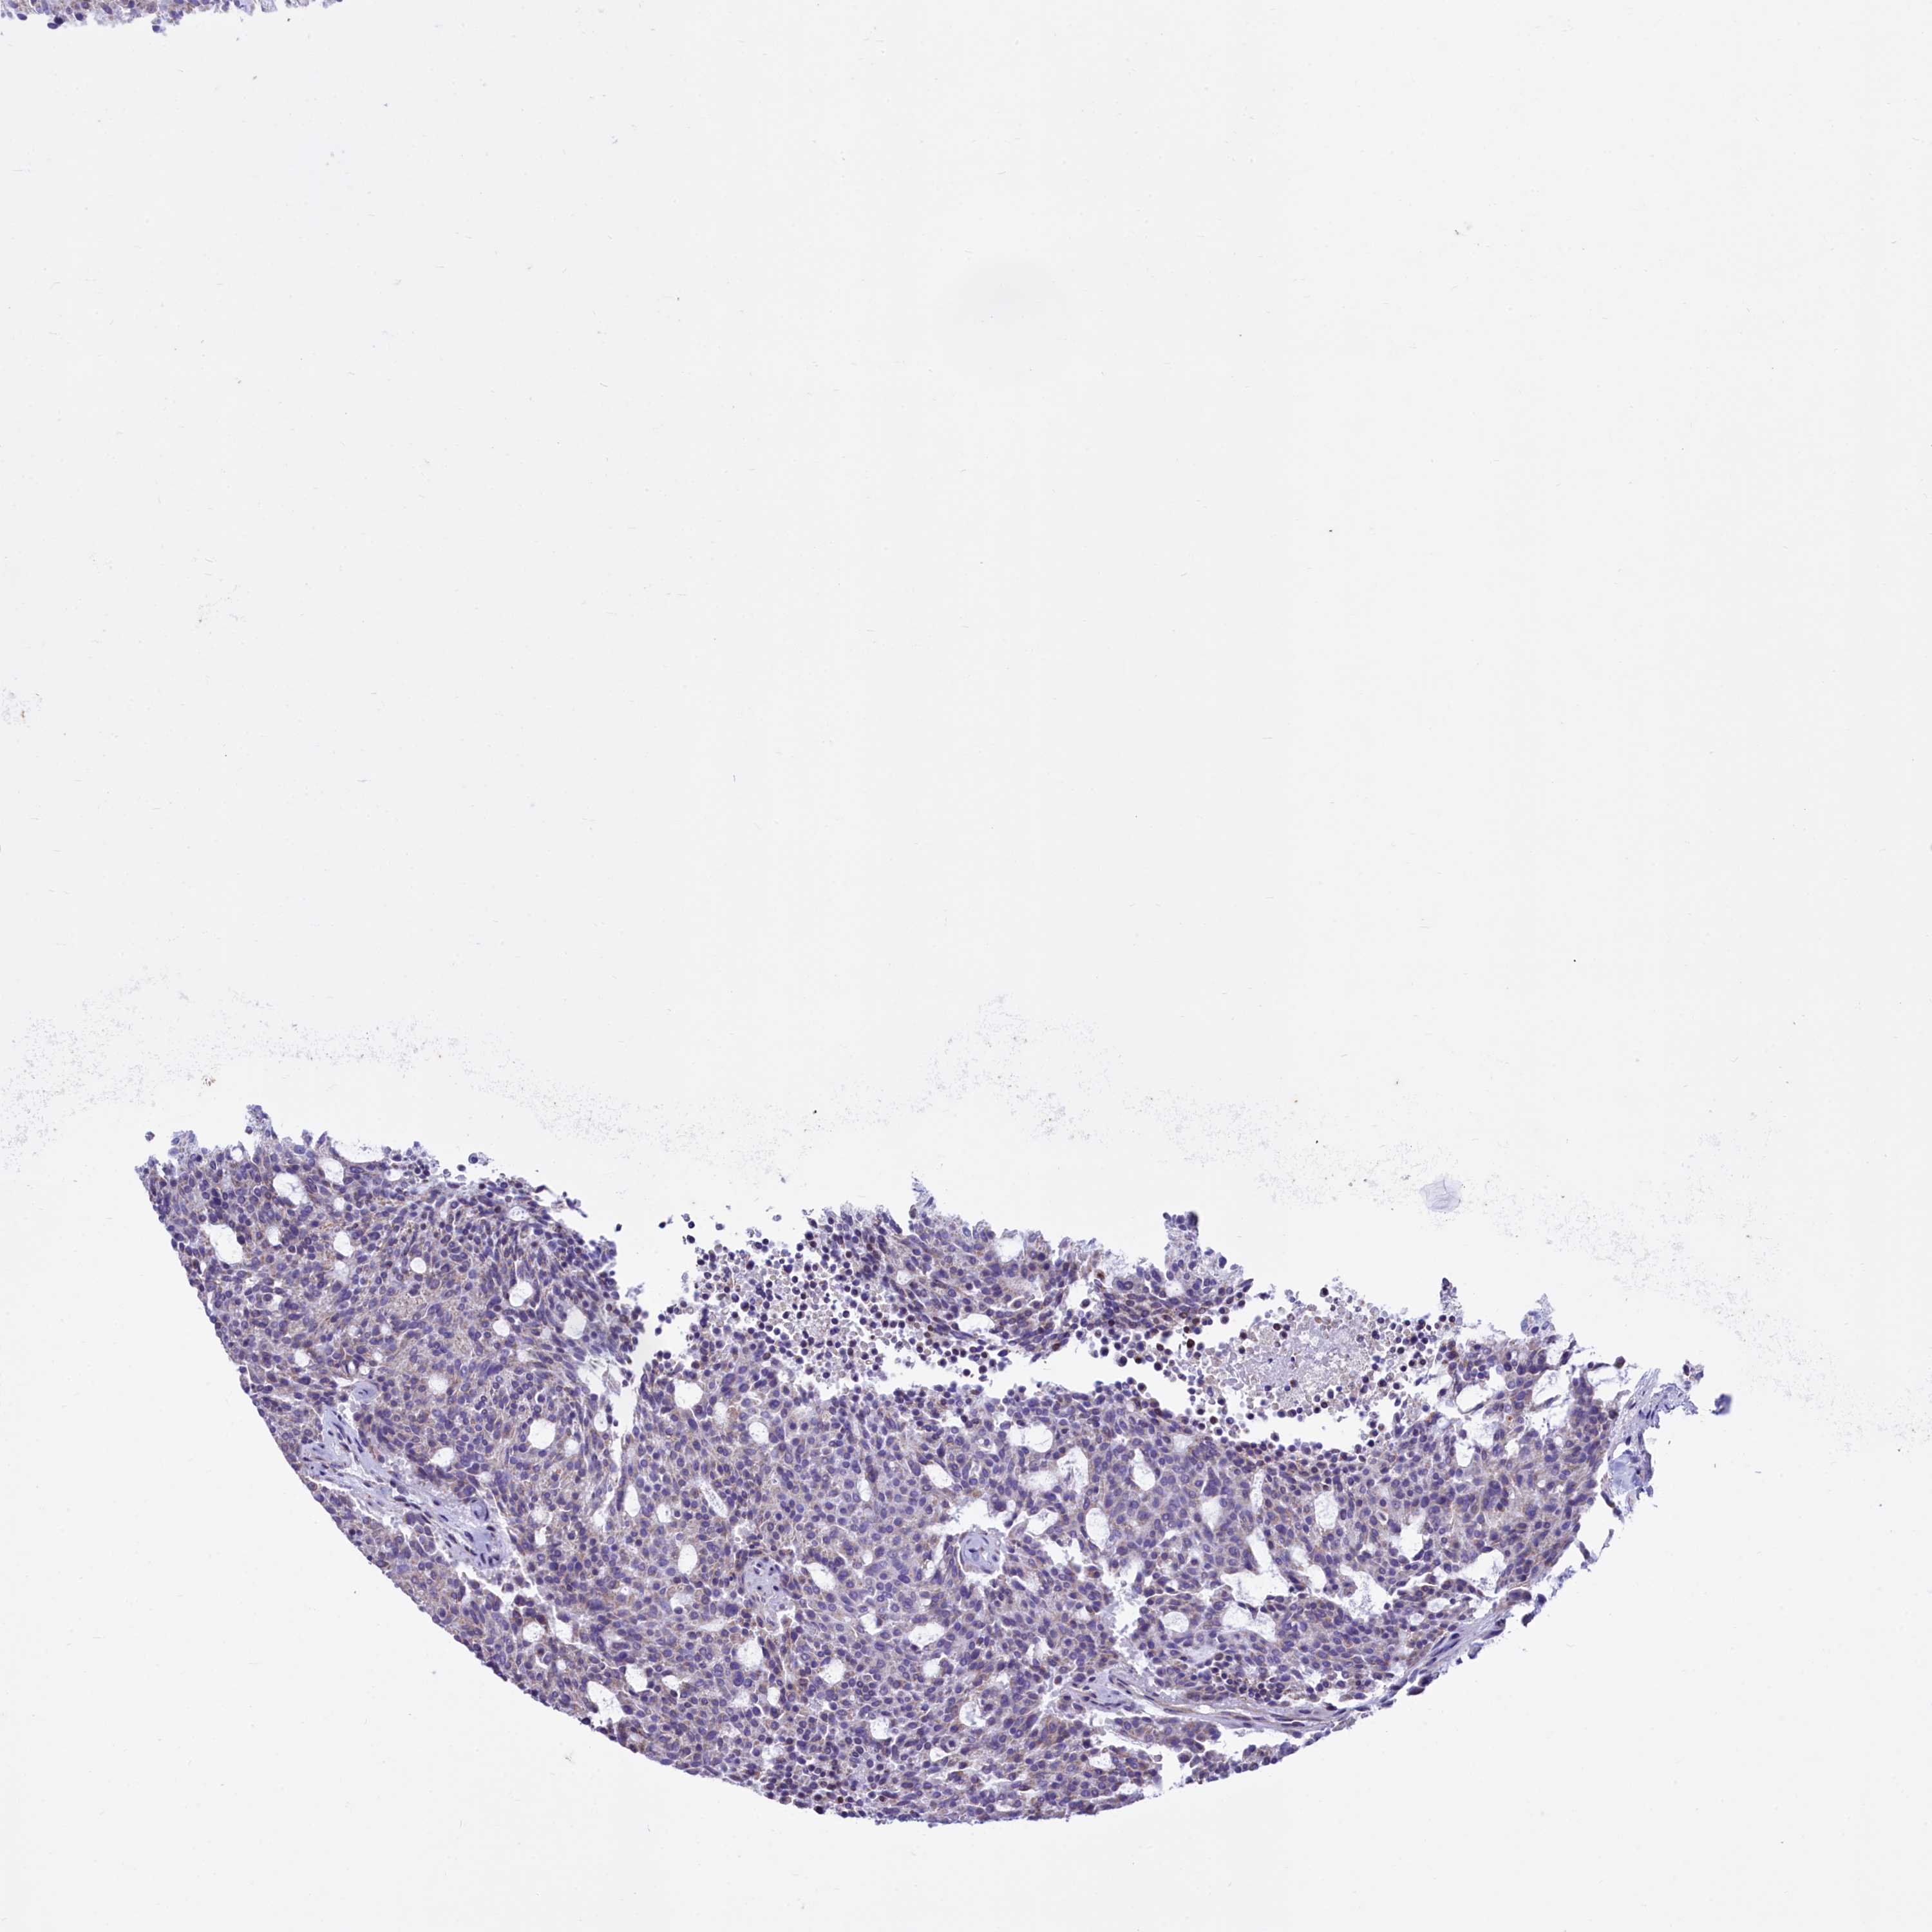

CARCINOID - Protein expressioni

A mouse-over function shows sample information and annotation data. Click on an image to view it in a full screen mode. Samples can be filtered based on level of antibody staining by selecting one or several of the following categories: high, medium, low and not detected. The assay and annotation is described here.

Each image is clickable and will lead to virtual microscopy that enables deeper exploration of all samples and also displays staining intensity scores, fraction scores and subcellular localization as well as patient and tissue information for each sample.

Antibody HPA040401

Staining

High

Intensity

Strong

Quantity

>75%

Location

Nuclear

Carcinoid, malignant, NOS

Carcinoma, NOS